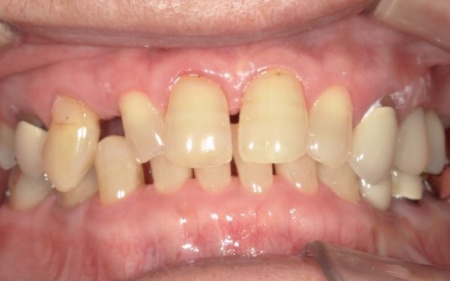

70代女性 歯根が割れた左下奥歯を抜きインプラントで噛み合わせを回復させた症例

レントゲン撮影を行って詳しく拝見したところ、左下奥歯(第1小臼歯)の歯根が割れていました。

まず、周辺組織に負担をかけないよう配慮しながら、慎重に左下奥歯(第1小臼歯)を抜きます。

抜歯後は骨や歯茎の回復を待ち、口腔内の状態が安定したことを確認して、インプラント埋入手術へ進みました。

後日、インプラントと骨がしっかりと結合したら、精密な型取りを行い、被せ物を作製します。

最後に完成した被せ物を装着し、痛みや違和感がないか、見た目や噛み合わせに問題がないかを確認して、治療を終了しました。